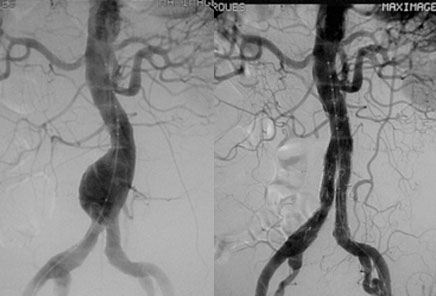

FOTO 1 – ILUSTRAÇÃO DE UM ANEURISMA DE AORTA E ILÍACAS

O tratamento tradicional através de cirurgia aberta, vem sendo substituído ao longo dos últimos 25 anos pelo chamado tratamento endovascular  sendo esta modalidade terapêutica menos invasiva e com consequente menor morbimortalidade.

O tratamento endovascular consiste na realização de pequenas incisões na  virilha ou ainda, de forma totalmente percutânea, na inserção de longos cateteres que carregam no seu interior uma endoprótese.  Este dispositivo consiste em um stent metálico recoberto por uma espécie de tecido que é posicionado utilizando aparelhos sofisticados de imagem radiológica conhecidos como angiográfos e em seguida liberado em um local sadio da aorta, reforçando suas paredes e evitando a passagem do sangue no local doente (aneurisma ou dissecção). Essa técnica promove uma recuperação mais rápida ao paciente com muito menos complicações e uma reduzida taxa de óbito quando comparada com a cirurgia aberta, e com isso permite o tratamento de pacientes com idade avançada e múltiplas comorbidades

FOTO 1 –  OPERATÓRIA DE UM ANEURISMA DE AORTA ABDOMINAL

FOTO 2 – IMAGEM OPERATÓRIA DO MESMO PACIENTE APÓS O IMPLANTE DA ENDOPRÓTESE EXCLUÍNDO O ANEURISMA